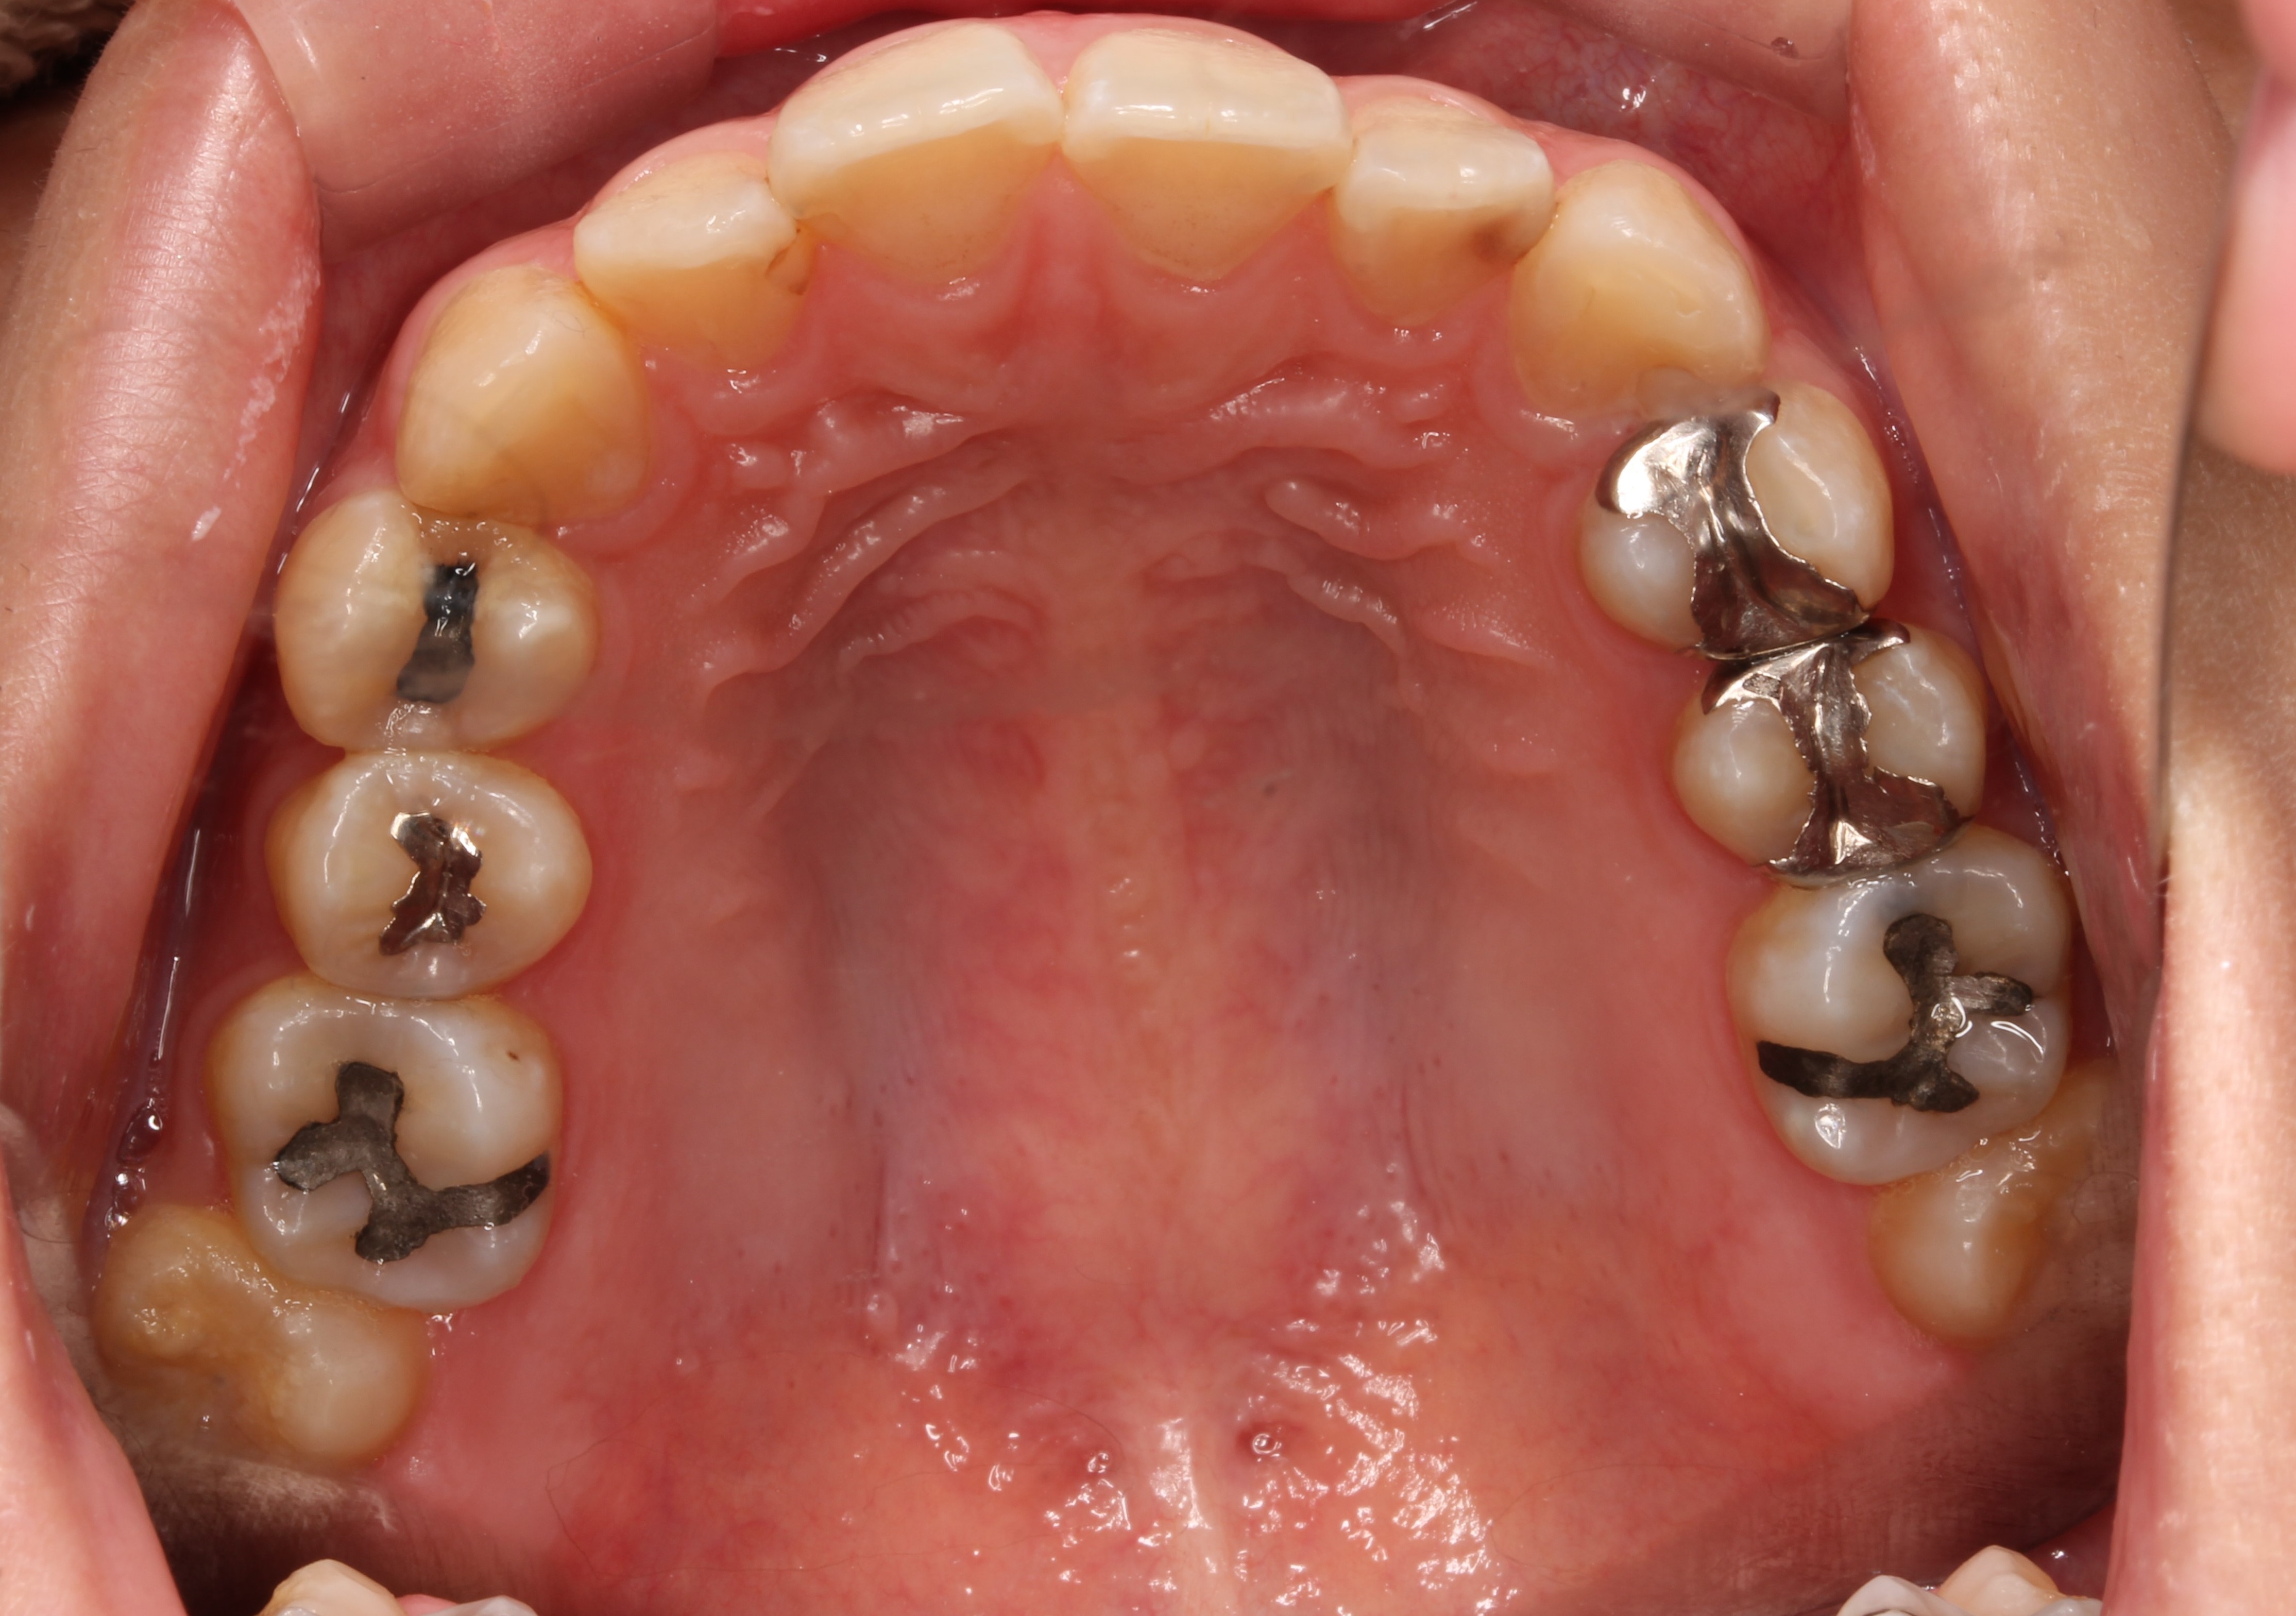

術前写真です。

上の歯には、3本のアマルガム金属と、3本のパラジウム合金が入っていました。

虫歯も数か所あります。